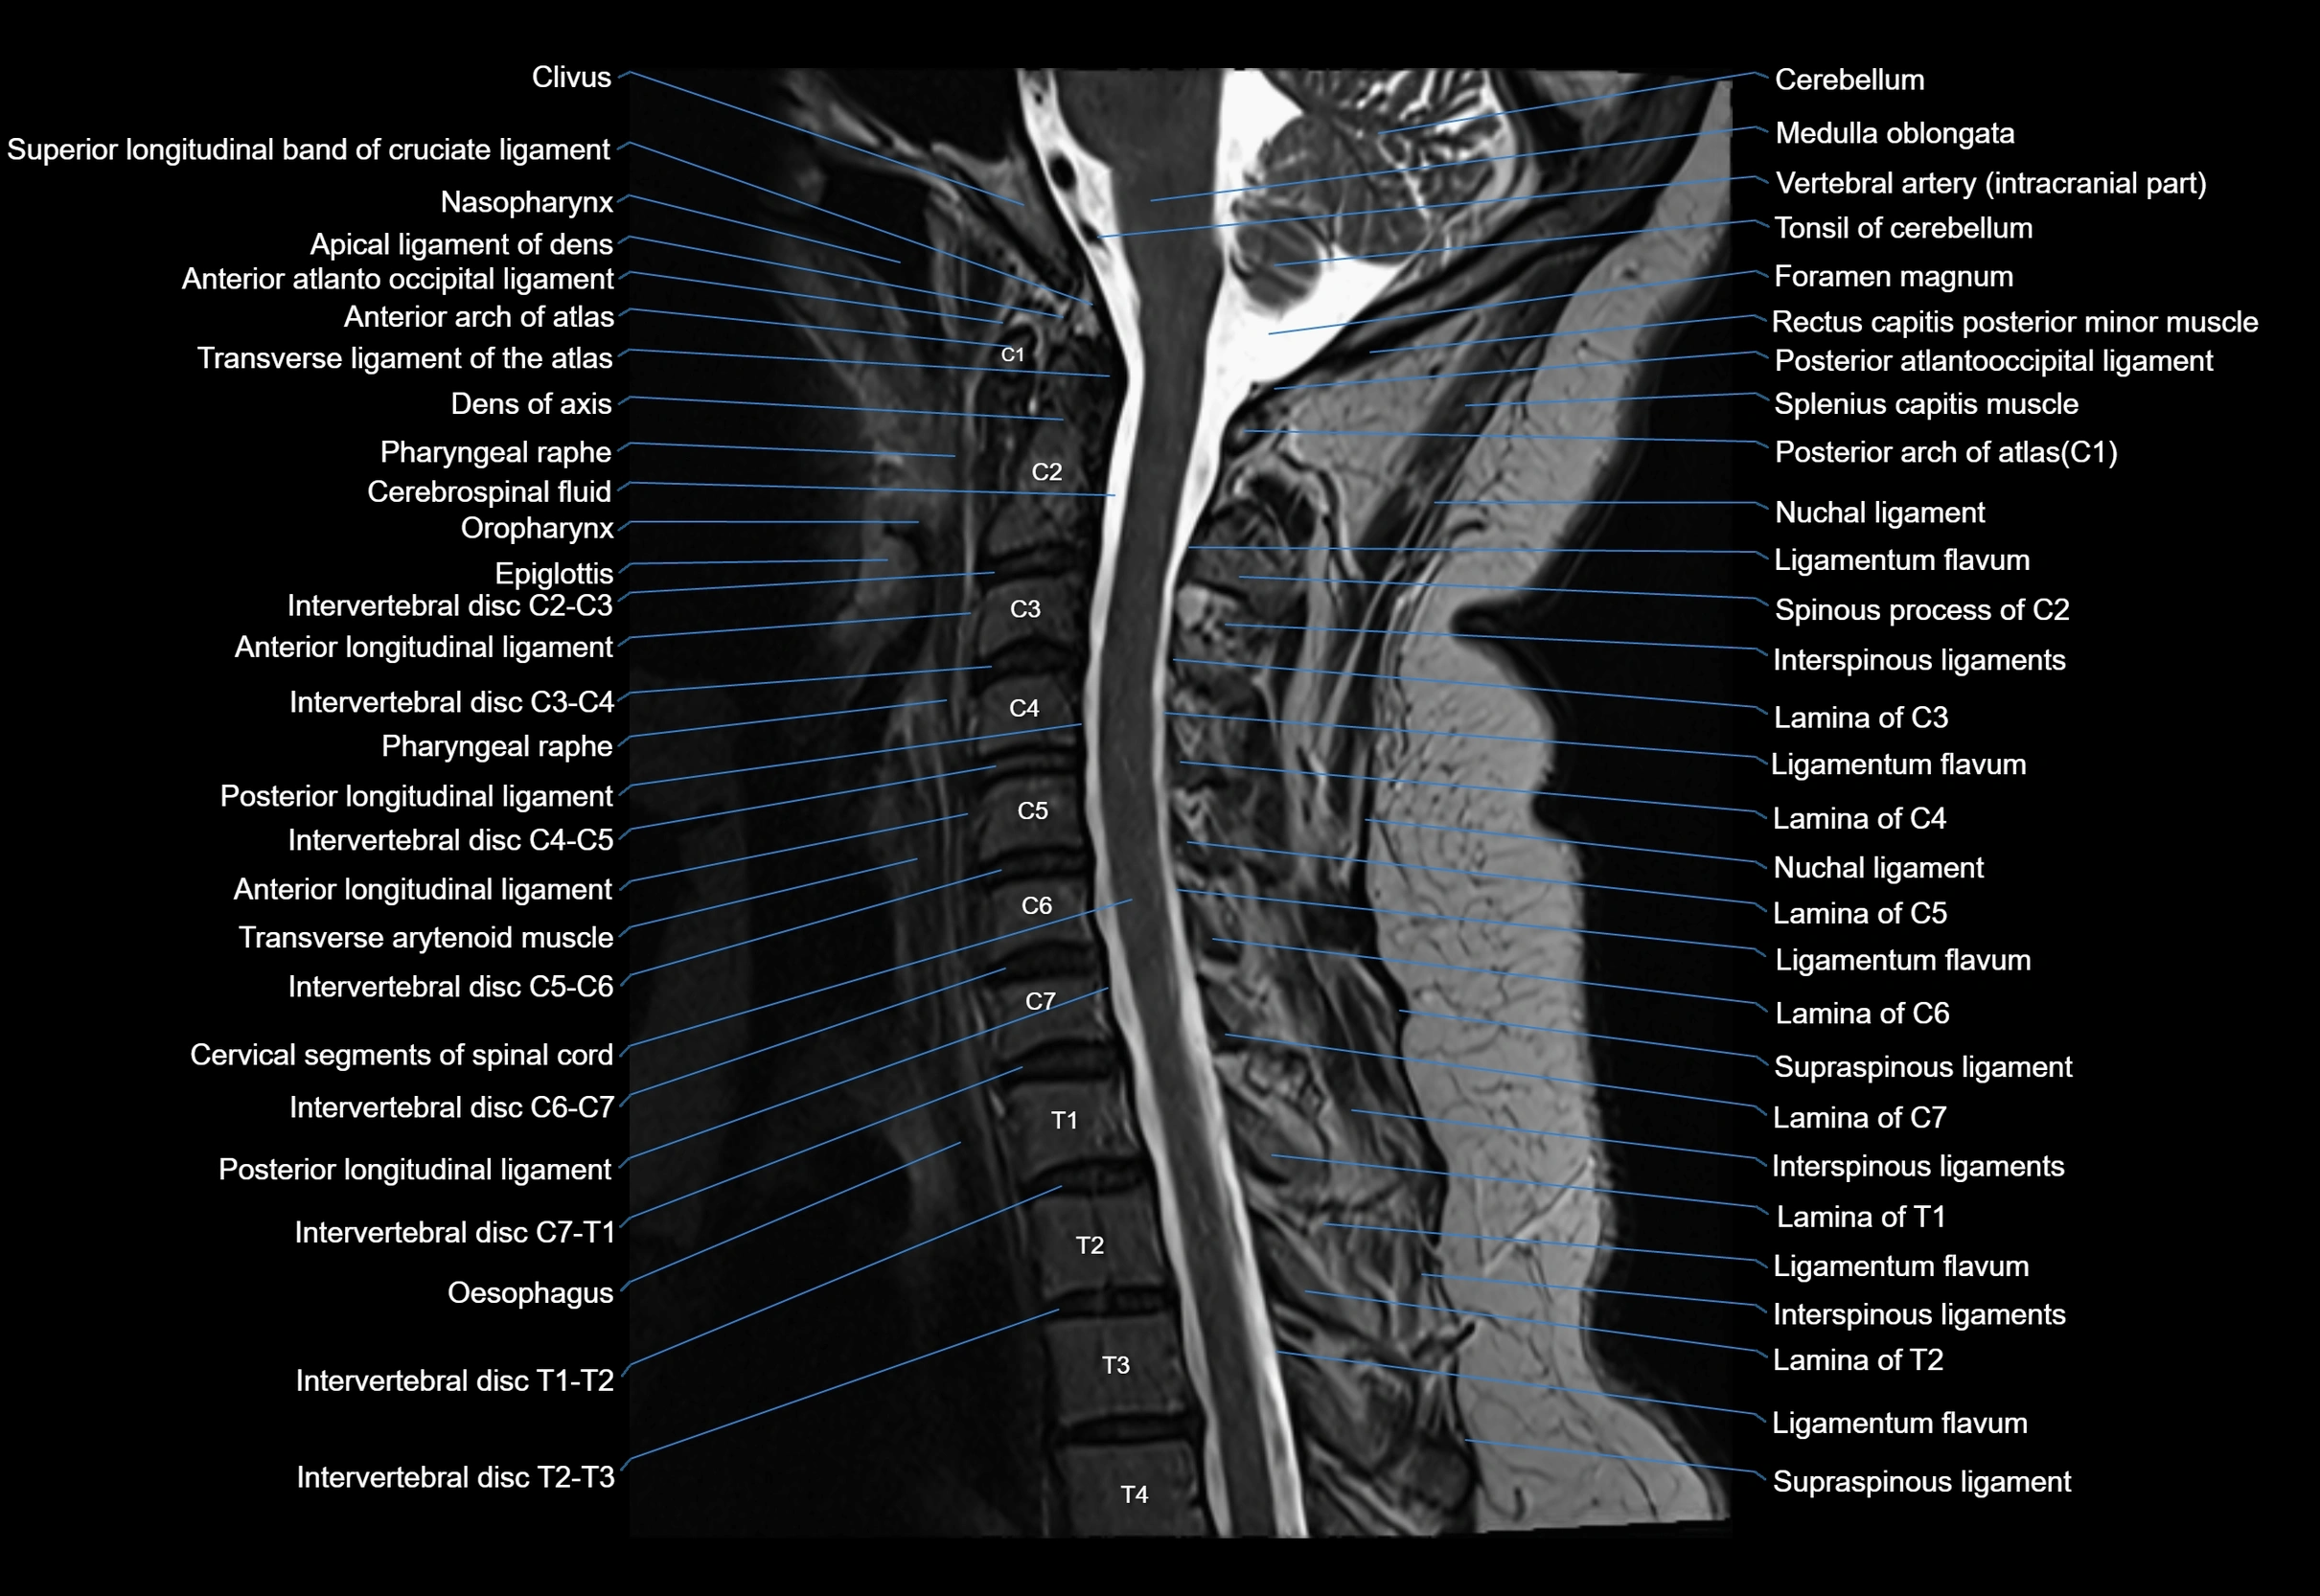

MRI appearance

T1-weighted images:

• Annular epiphysis: Low signal cortical rim at the vertebral margin

• Adjacent marrow: Intermediate-to-high signal in the vertebral body

• Disc interface: Clear delineation between bone and annulus

T2-weighted images:

• Annular epiphysis: Low signal intensity line

• Endplate cartilage (in younger patients): Intermediate signal

• Intervertebral disc: High signal nucleus pulposus

STIR:

• Annular epiphysis: Low signal cortical rim

• Adjacent marrow: Suppressed fat signal with preserved bony outline

• Utility: Highlights marrow and endplate interface in developing spine

MRI image

image